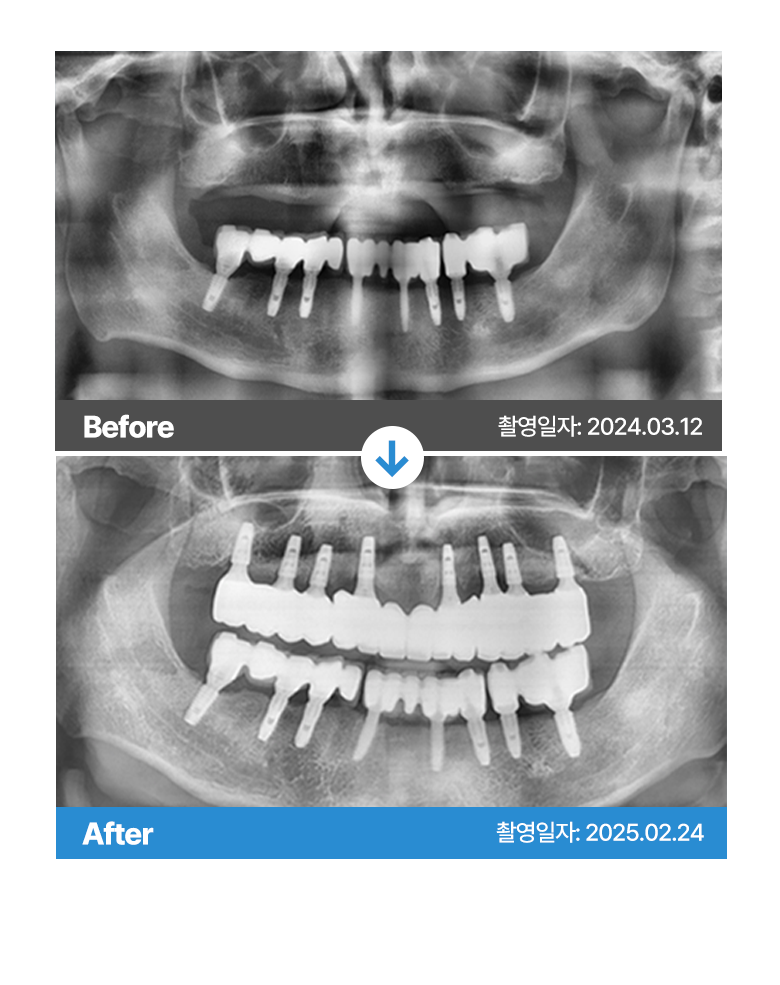

* 본원에서 치료 받으신 환자분의 사례로

환자분의 동의를 얻어 활용함을 안내드립니다.

개인에 따라 결과차이, 부작용 등이 발생할 수 있으므로

의료진과의 상담을 통해 신중히 결정하시기 바랍니다.

* 본원에서 치료 받으신 환자분의 사례로 2차적인 가공이 없으며, 환자분의 동의를 얻어 활용함을 안내드립니다.

개인에 따라 결과차이, 부작용 등이 발생할 수 있으므로 의료진과의 상담을 통해 신중히 결정하시기 바랍니다.